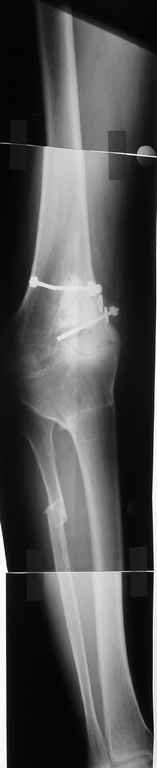

Пациент 59 лет, в 1982 году по поводу остеобластокластомы была выполнена частичная резекция проксимального отдела бедра с пластикой дефекта костно-хрящевым трансплантатом (моноблок)с фиксацией металлическими стяжками.

В последующем по поводу деформирующего артроза выполнена корригирущая остеотомия большеберцовой кости. Исход представлен на рентгенограмме. В настоящий момент пациента беспокоят боли  в коленном суставе, деформация, и ограничение движений. Варусная деформация коленного сустава 20, движения сгибание 115, разгибание 150, ходит с тростью, выраженная хромота, работа не связана с физическими нагрузками. Правый коленный сустав без патологии. Уважаемые коллеги просим высказать своё мнение - артродез  коленного сустава или эндопротезирование.